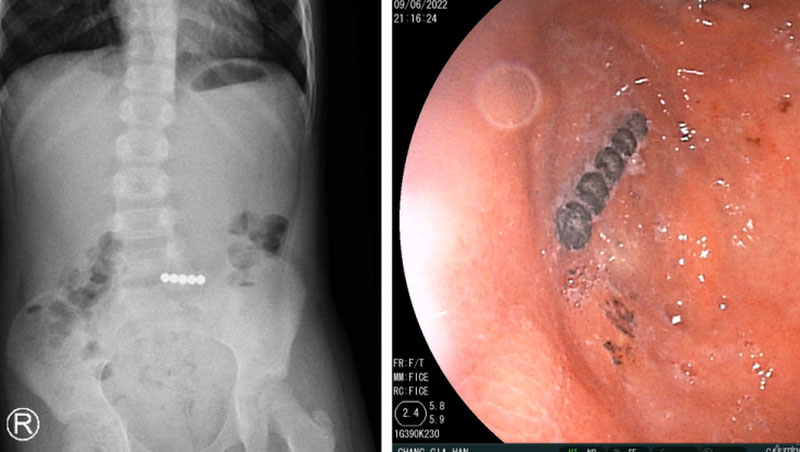

Hình ảnh phim X-quang và dị vật trong nội soi. Ảnh: BVCC

Tại bệnh viện, bệnh nhi biểu hiện đau bụng, nôn ói, hốt hoảng, được các bác sĩ hỗ trợ hô hấp thở oxy. Kết quả chụp X-quang bụng không sửa soạn phát hiện dị vật ở ruột non.Các bác sĩ đã tiến hành hội chẩn các bác sĩ chuyên khoa tiêu hóa và phối hợp với các bác sĩ ngoại khoa tiến hành nội soi đường tiêu hóa cấp cứu và nội soi ổ bụng, đẩy dị vật từ ruột non lên dạ dày cho bác sĩ tiêu hóa nội soi gắp ra 5 viên bi nam châm dính liền nhau.